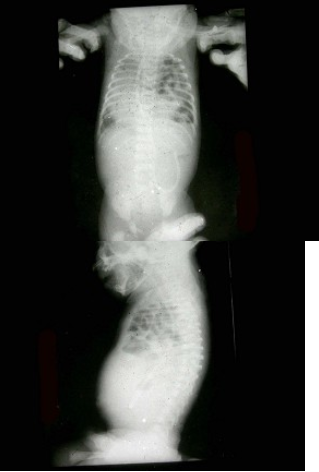

32、单项选择题

男,出生后2天。哭闹不止,腹胀。如图所示,最可能的诊断为()

A.肠套叠

B.肠闭锁

C.胎粪性腹膜炎

D.肠扭转

E.肠狭窄